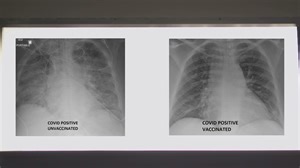

COVID-19 lung x-rays show difference vaccination can make

Jul 30, 2021

ksdk.com

Doctor Examines Lung X-Rays of Vaccinated and Unvaccinated CO

…

Aug 9, 2021

nbcmiami.com

Here's how lung X-rays look between vaccinated and unvaccin

Nov 8, 2021

cbs8.com